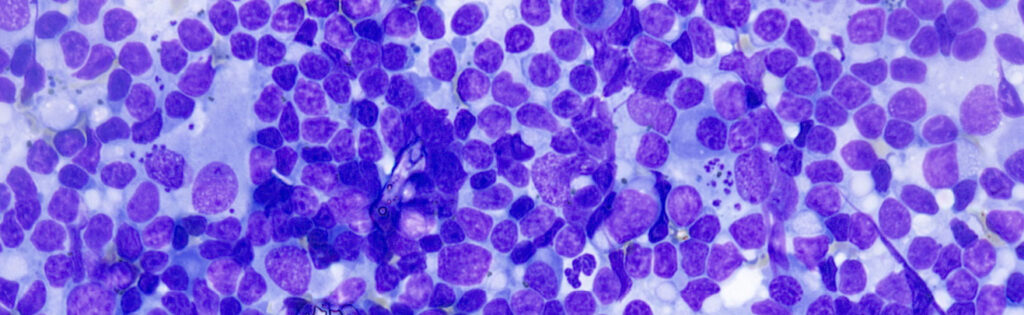

Para obtener la máxima sensibilidad, las muestras recomendadas son el aspirado de médula ósea y el aspirado de linfonodo, ya que suelen presentar una mayor carga parasitaria.

También es posible trabajar con otras muestras como sangre periférica, hisopos de lesiones cutáneas o líquido sinovial. Estas muestras son válidas, aunque no se consideran óptimas y están más sujetas a criterios de inclusión relacionados con la carga parasitaria, algo que siempre valoramos previamente en el laboratorio para garantizar la fiabilidad del resultado.

Imágenes cedidas por Urano Diagnostics – Uranolab